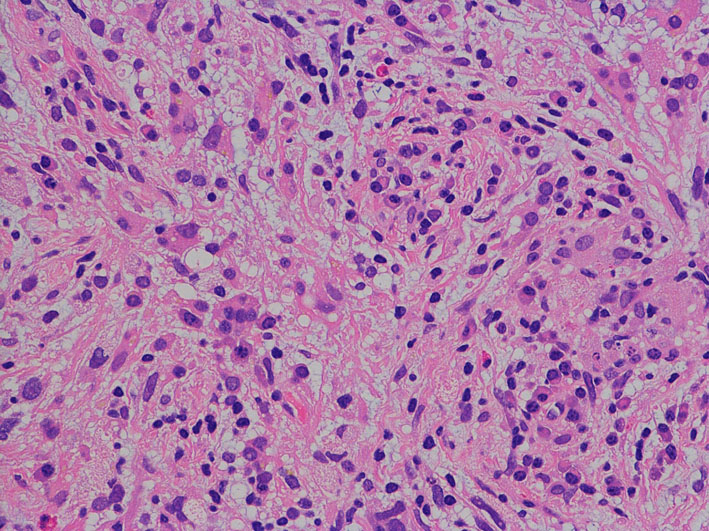

退形成性星細胞腫の病理組織

- びまん性星細胞腫と膠芽腫との中間の所見です

- 膠芽腫との違いは,腫瘍細胞が死んでいる部分(壊死 necrosis)がないことが最大の特長です

- びまん性星細胞腫との違いは,細胞核の異型性 anaplastyと分裂能の高さです,核の大きさが大小不同で歪んだ形をしています

- 画像で見えるよりかなり広範囲に広がっていて single cell infiltrationといいます

核の異型性,多核細胞が目立つ例です。グレード3の典型例です。

核異型性は乏しいのですが,細胞密度が高い例で,MIB-1染色率は12%です。グレード2と鑑別しづらいことがしばしばです。核分裂が散見されたりMIB-1染色率が高い場合はグレード3として治療をしたほうがいいでしょう。